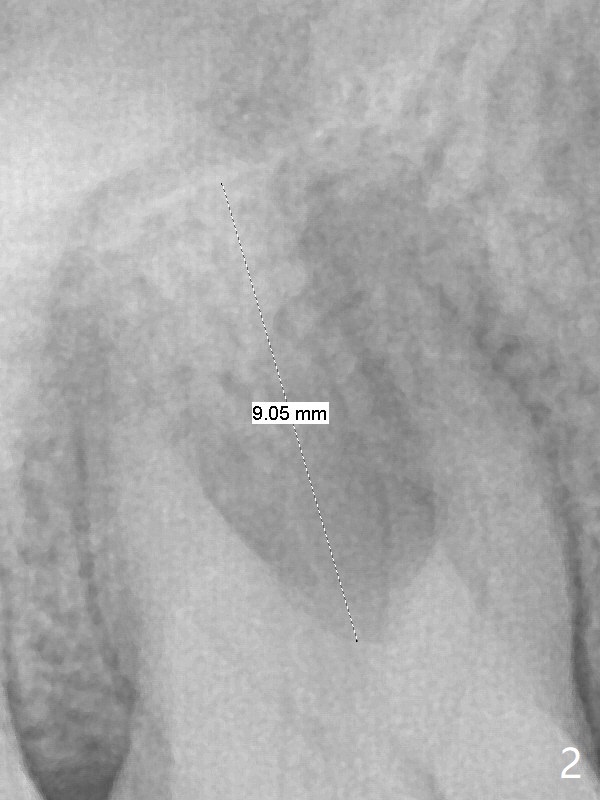

A 53-year-old woman has crack tooth symptom at #3 with apparently a vertical crack line on PA (Fig.1 arrow), suggesting bruxism. The latter may be easily associated with abutment screw loosening. To avoid this complication, a tissue-level implant will be placed (Fig.3). After extraction, the initial depth of osteotomy in the septum will be 7 mm (Fig.2). Find a pointed drill. Take preop photos to show the possible buccal crack line.